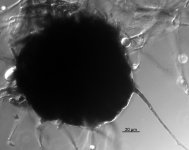

| Species Name: | Macrophomina phaseolina |

| Taxonomy: | FUNGI Ascomycota, Dothideomycetes, Botryosphaeriales, Botryosphaeriaceae |

| Characters: | CELLULOLYTIC - // CULTURE CONDITIONS no conidia observed - // CULTURE CONDITIONS sclerotia produced - // CYCLOHEXIMIDE sensitive - // HUMAN/ ANIMAL PATHOGEN dual infection in renal transplant patient - Tan DHS, Sigler L, Gibas C, Fong IW, Med Mycol 46:285-292, 2008 // MOLECULAR SYSTEMATICS 100% identical in pair-wise comparison with UAMH 10586 (ATCC 62589) - Tan DHS, Sigler L, Gibas C, Fong IW, Med Mycol 46:285-292, 2008 // MOLECULAR SYSTEMATICS 100% ITS similariity in pair-wise comparison with UAMH 10586 (ATCC 62589) - // MOLECULAR SYSTEMATICS BLAST match 98% identity to Macrophomina phaseolina - // PIGMENT dark brown - // PIGMENT pink - // THERMOTOLERANT good growth @ 35 C - (Click for publications citing UAMH 10549) |